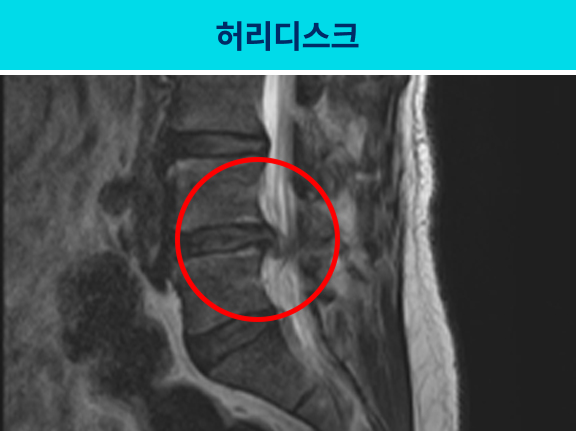

허리디스크와는 달리 허리통증은 심하지 않거나 거의 없지만, 신경이 지나는 길목인 엉치,

골반부터 허벅지, 종아리, 발까지 통증이 발생하는 것이 주요한 차이점입니다.